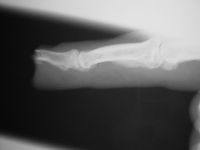

| The final result

was compromised by bone loss. The initial bone loss

was severe enough to warrant bone graft, but this

was contraindicated by the recent infection. |

| Over time, loss

of this structural support led to shortening and a

hook nail deformity. |

| Result at one